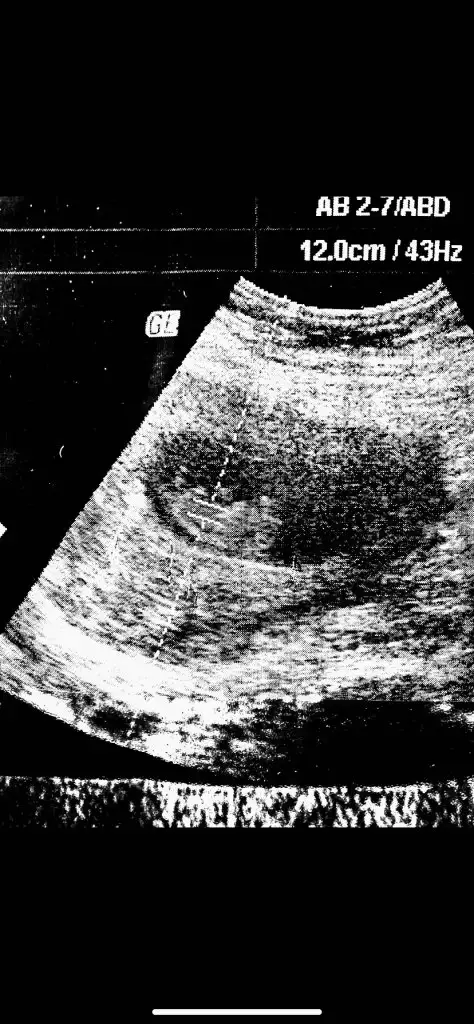

Amin sağlıklı hayırlı olsunlar inşallahYaa hadi bakalım hayırlısı inşallah hepimiz için![]()